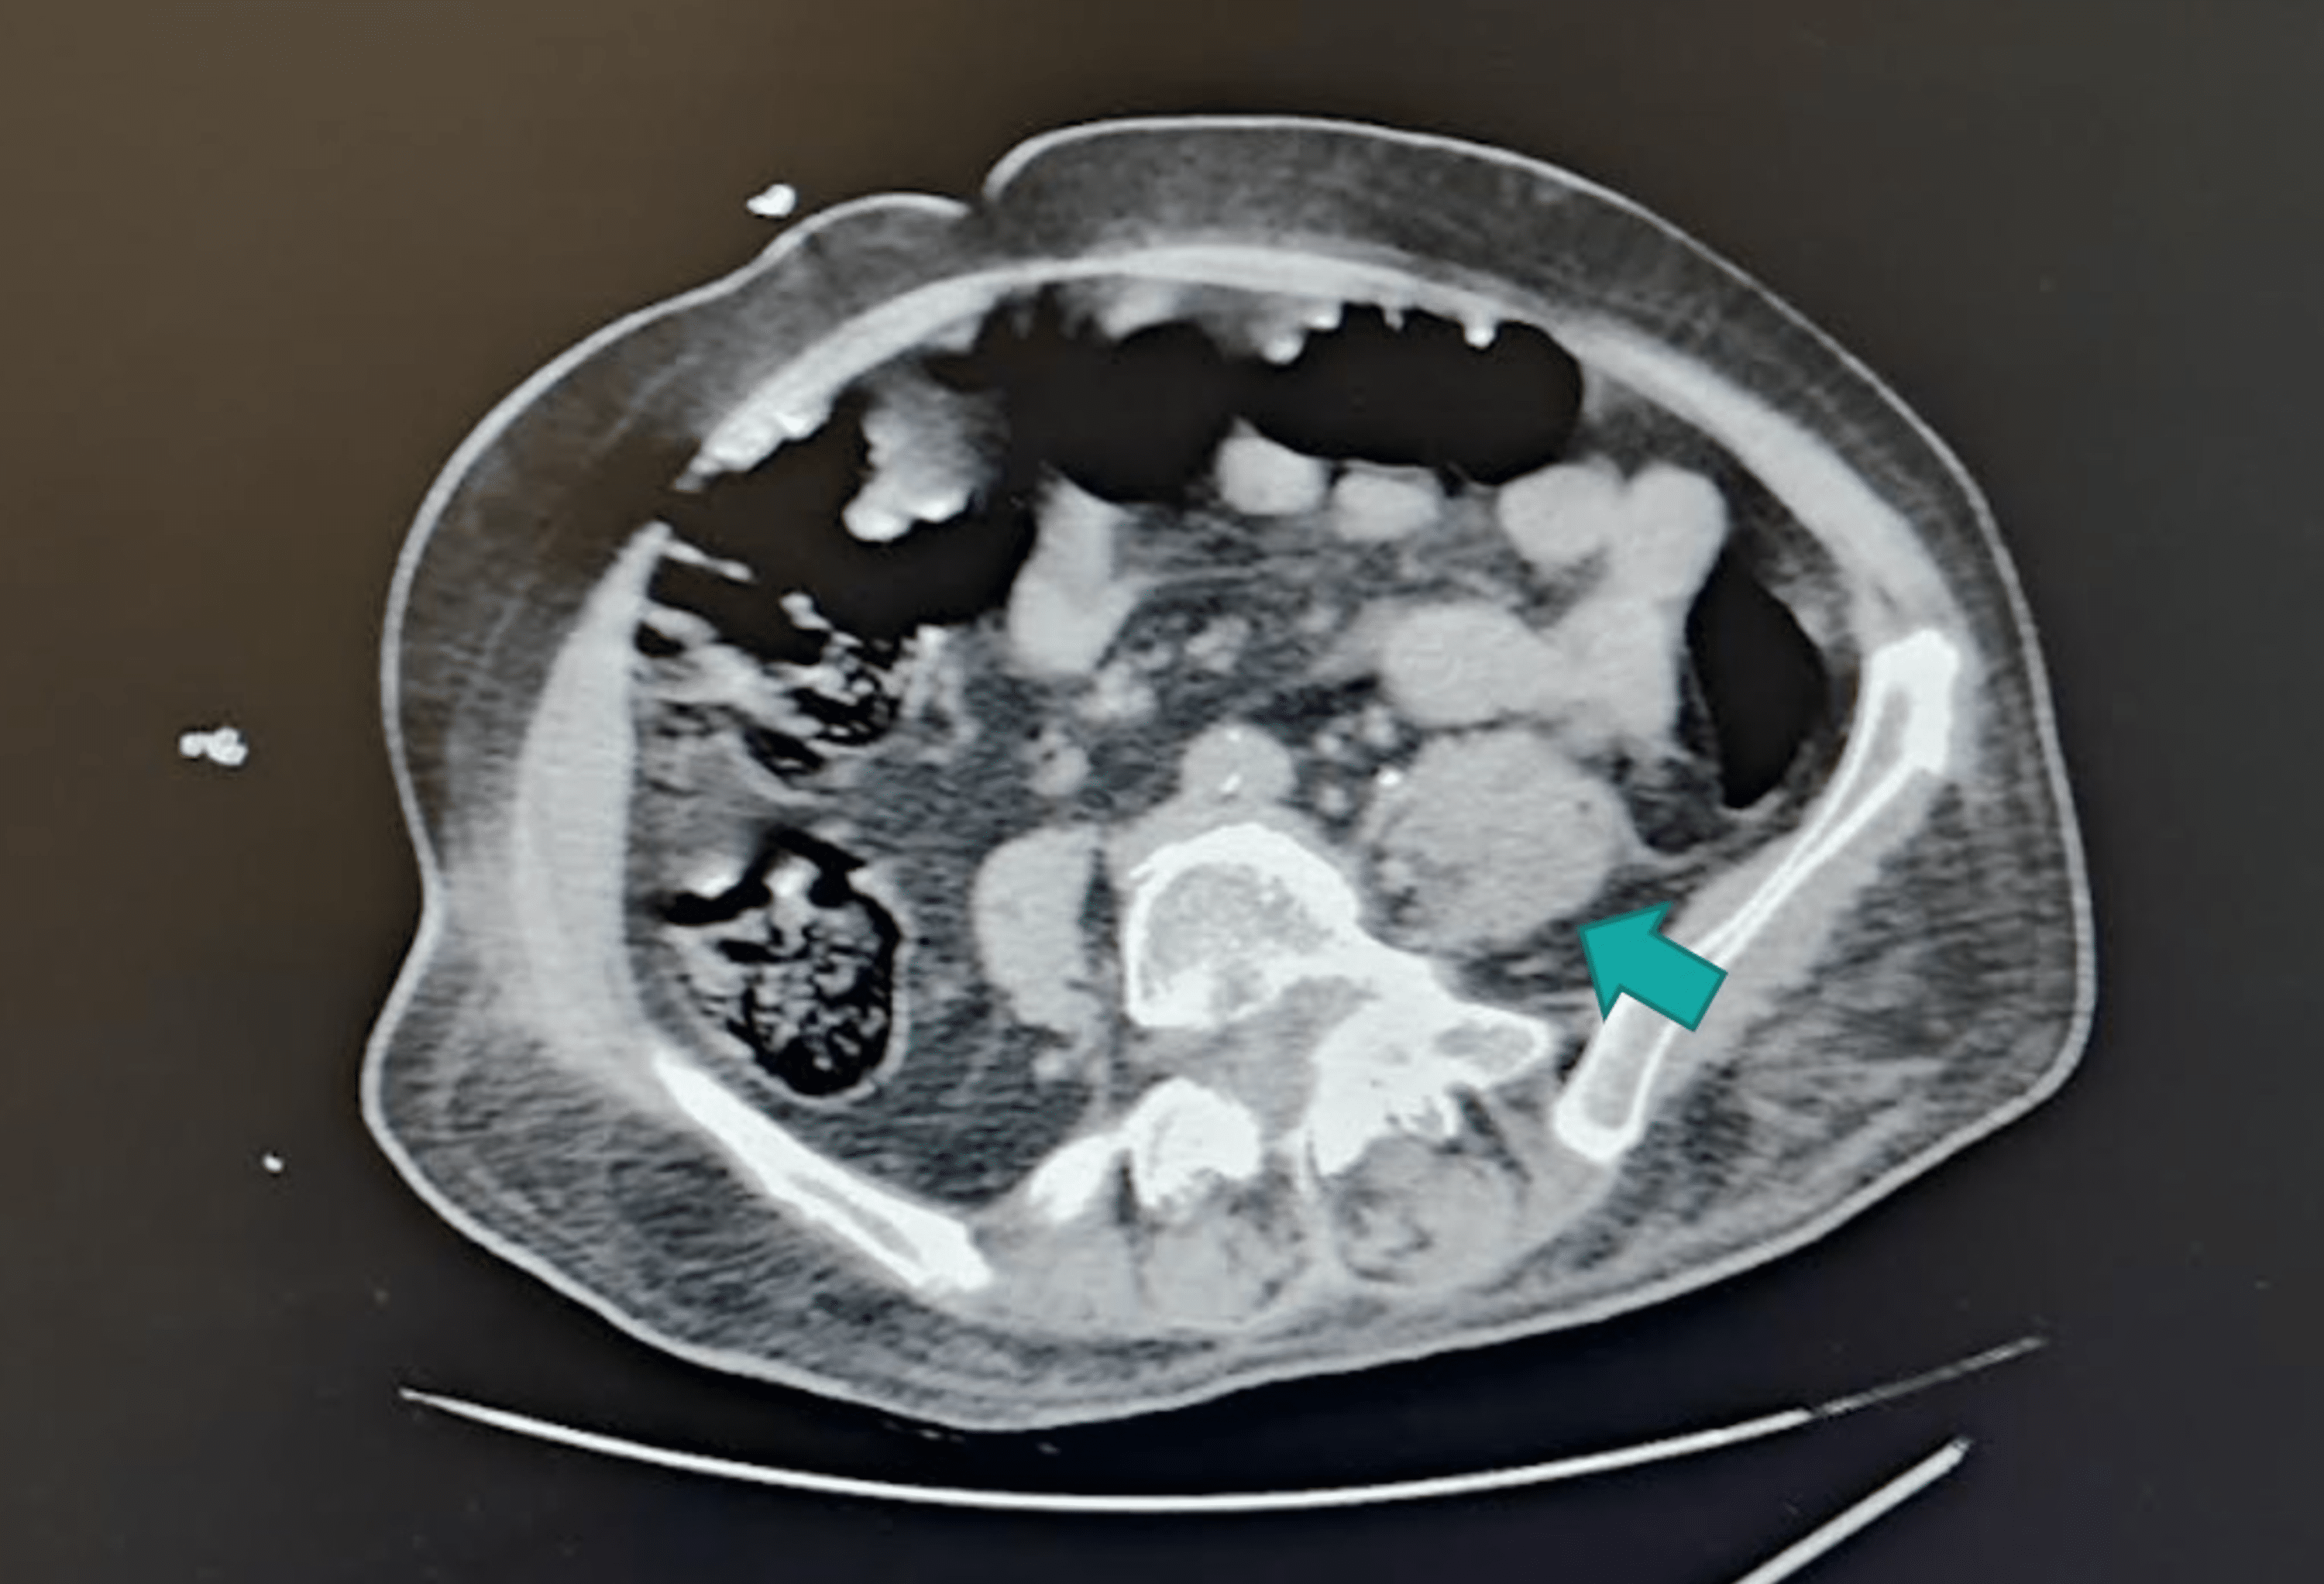

Psoas Abscess Ct Scan Pott's Disease Psoas Abscess Pott’s spine also called spinal tuberculosis occurs due to extra pulmonary tuberculosis. We report a case of. Bilateral psoas abscesses are uncommon in pott's disease. Bilateral psoas abscesses are uncommon in pott's disease. Tb of the vertebra (pott's disease) is the most common cause of secondary psoas abscess, in developing countries. In general, pott's disease causes inflammation process in the. Pott's Disease Psoas Abscess.